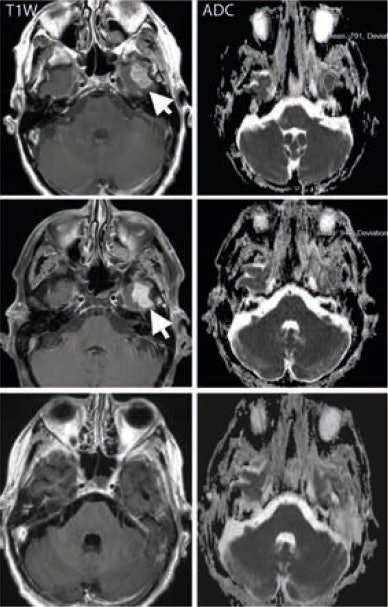

MRI has emerged as an interesting modality, as it can provide information on tumor vascularity and cellularity, he explained. "MR may enable earlier identification of treatment effects, as well as detect adverse effects from treatment. Diffusion-weighted imaging can help measure cellularity and dynamic contrast-enhanced MRI enables us to assess vascularity. And then we can also look at the complexity of the tumor environment, i.e., proteins, using magnetization transfer MR," he said.

MR's particular value is that it gives better image definition of the tumor in areas such as the brain, tumors in the extremities of the body, and sarcoma and soft-tissue sarcoma, where CT traditionally has difficulty.

Another specific contribution for MRI will be in the surveillance of adverse effects. "You may not identify these complications on CT or PET. MRI with its exquisite soft tissue contrast can demonstrate complications that can affect patient management."